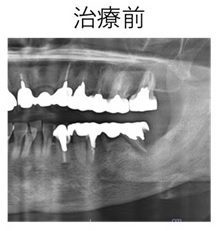

インプラント治療(インプラント治療は自由診療であるため、原則保険の適用はされません。)

インプラント治療は、歯を失った方に対して顎の骨にチタン製の人工歯根(デンタルインプラント)を埋入し、咬合の再建を行う治療です。

インプラントのメリットは、他の歯に依存せずに単独で機能するため、周囲の健康な歯を削る必要がありません。また、しっかりと固定されることで、入れ歯のように動いたり、外れたりする心配がありません。さらに、噛む力が強く、硬い食べ物も問題なく食べられます。見た目も自然で、自信を持って笑顔を見せることができます。

インプラント治療は、適切な診断と計画が重要です。まず、口腔内の状態を詳細に診査し、CTスキャンなどのX線検査で骨の量や質を確認します。

インプラント体を埋入する位置は、血管や神経などの解剖学的に危険な構造を避けつつ、隣在する歯との水平的な位置関係や噛み合わせのバランスを加味しながら決定されます。

最新の3Dシュミレーションソフトを用いて解析を行い、この解析データを元に手術用ステントを作製し、専用ドリルを用いて手術が行われます。

症例① 歯根破折のため左臼歯部を抜歯しインプラント治療を行なった治療例。